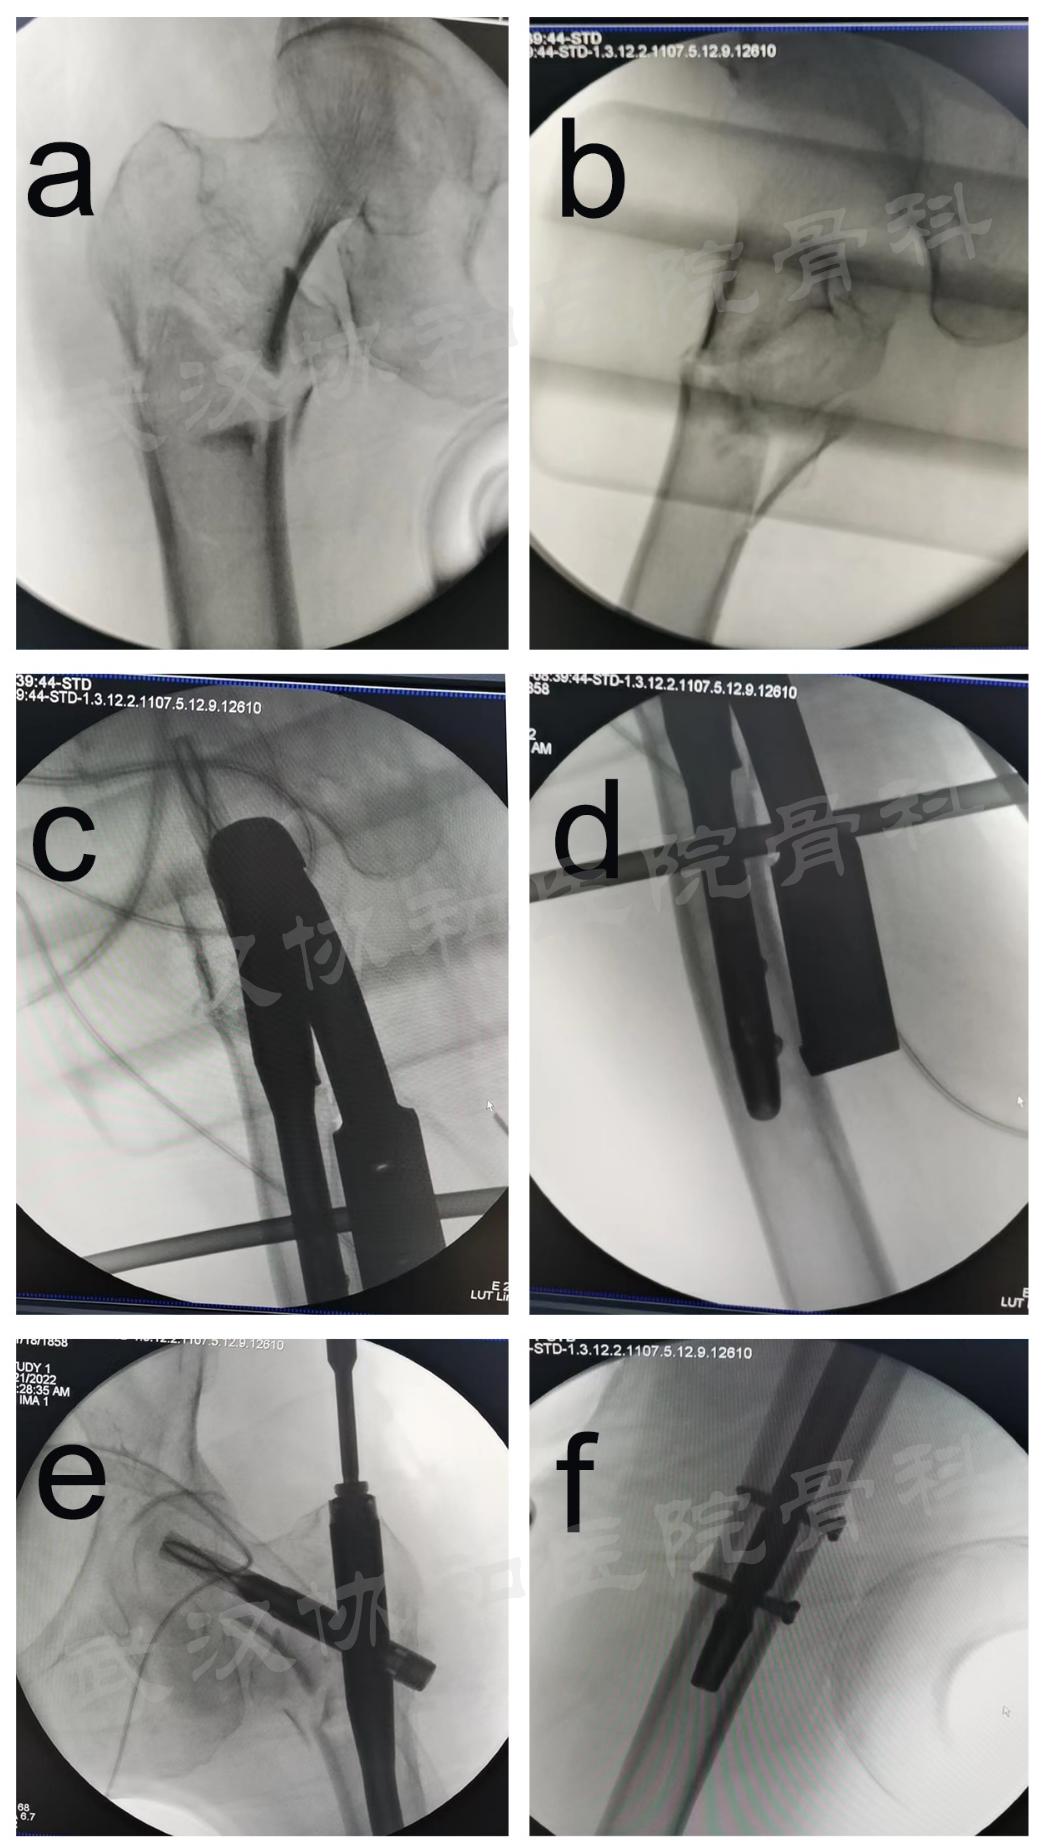

术中DRTR应用图

术中透视图。DRTR复位后股骨转子间骨折前后位(a)和外侧位(b)影像学图;(c、d)置钉后的侧位图;(e、f)置钉后的前后位图